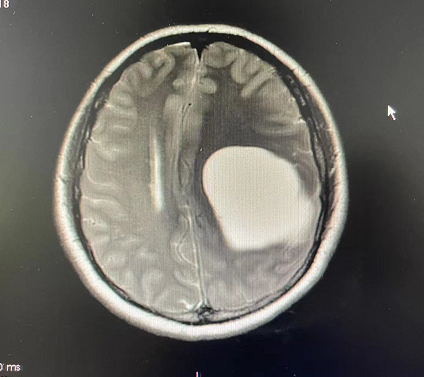

警惕!女子右手发麻无力连筷子都用不了,以为颈椎病竟是脑肿瘤

人民网科普